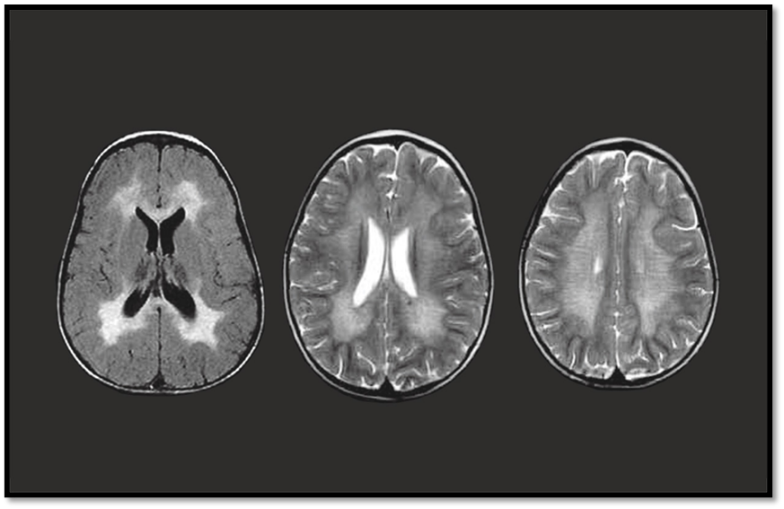

MRI Brain

Shows symmetrical white matter demyelination (especially periventricular regions)

Allogenic hematopoietic stem cell transplantation (HSCT) is considered the standard treatment for presymptomatic and early-symptomatic adult and late-juvenile forms of metachromatic leukodystrophy (MLD), though its benefits in early-onset cases are limited due to rapid disease progression. Following transplantation, patients may initially experience worsening MRI abnormalities and symptoms, likely due to chemotherapy-related neurotoxicity and the delay in full engraftment of donor cells within the brain. However, when performed early in the disease course, HSCT can lead to long-term stabilization or even improvement in white matter changes. Traditionally, the therapeutic effect of HSCT was believed to occur through cross-correction, where donor-derived macrophages and microglia provide functional arylsulfatase A (ASA) to the patient’s deficient neural cells. This mechanism, however, has been called into question, as studies have shown that ASA secreted by these donor cells often lacks the mannose-6-phosphate necessary for cellular uptake. Furthermore, postmortem analysis of HSCT-treated MLD patients revealed ASA presence only in donor macrophages—not in oligodendrocytes or astrocytes—suggesting that cross-correction may play a minimal role. Instead, an alternative mechanism has been proposed in which donor macrophages contribute metabolically by clearing sulfatide buildup and exerting anti-inflammatory effects that promote oligodendrocyte survival and remyelination. This is supported by findings of higher oligodendrocyte counts and signs of remyelination in transplanted patients. Similar observations have been made in HSCT-treated mouse models of Krabbe disease, where benefits occurred despite limited cross-correction, further highlighting the role of donor-derived immune cells in reducing neuroinflammation. Despite these therapeutic potentials, HSCT carries significant risks, including graft-versus-host disease, infections, toxicity, chronic rejection, and increased malignancy risk, with mortality rates around 10–15%, and even higher in some patient groups.

Part 1: Evolution of brain MRI in patients 1 and 2 and, as an example, evolution of white matter abnormalities in a patient successfully transplanted (axial T2?weighted images shown). In the two deceased patients, white matter abnormalities increase, especially in patient 1. The successfully transplanted patient illustrates improvement of leukodystrophic changes 4 years after HSCT. Part 2: Donor cells reach the brain of transplanted MLD patients. (A) Stain with Klüver (blue dye for myelin) and periodic acid Schiff (PAS, pink, stain for sulfatides in macrophages) of the cerebral periventricular white matter of an untreated MLD patient (patient 5) shows loss of myelin and abundance of cells loaded with PAS?positive granular material. (B) Hematoxylin & Eosin stain of the frontal subcortical white matter of a HSCT?treated patient (patient 1) shows the presence of macrophages with intense eosinophilic cytoplasm (arrows) next to macrophages loaded with clearer granular material. (C) A Klüver?PAS stain of the same region of this patient confirms the presence of a double population of macrophages, more (open arrows) and less (closed arrows) intensely PAS positive. (D) Toluidine blue stain of the parietal white matter of this HSCT?treated patient (patient 2) reveals that only a subset of macrophages is metachromatic (purple, i.e., loaded with sulfatides), the remaining being orthochromatic (brown) and as such able to degrade sulfatides. (E) Metabolic competence of a subset of macrophages in the white matter of a HSCT?treated patient (patient 1) is confirmed by their ability to digest sulfatides, as shown in this Oil Red O stain for neutral fats. (F) In this patient, FISH against the X and Y chromosomes confirms cells of both sexes.